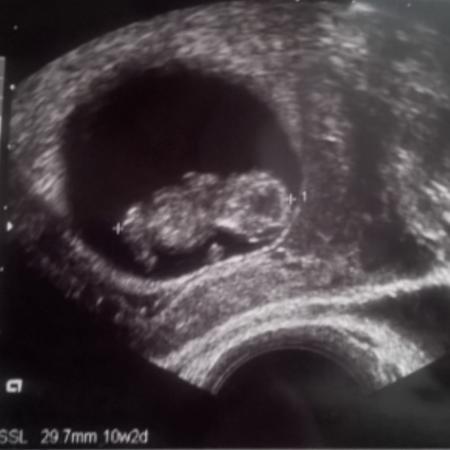

Also er wird wohl 8 mm gemeint haben, das Bild passt auf die 9ssw. Hänge mal mein Bild von der 9ssw an.

Bild zu